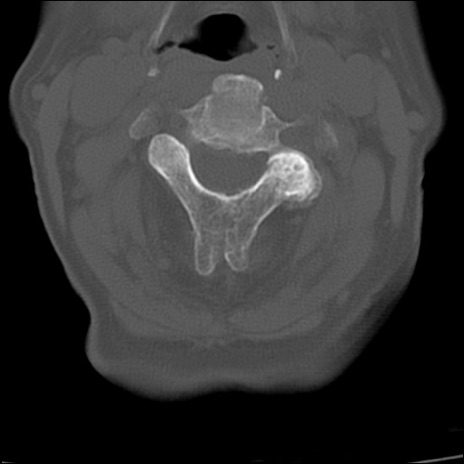

症例48 頚椎CT(横断像)

頚椎CT